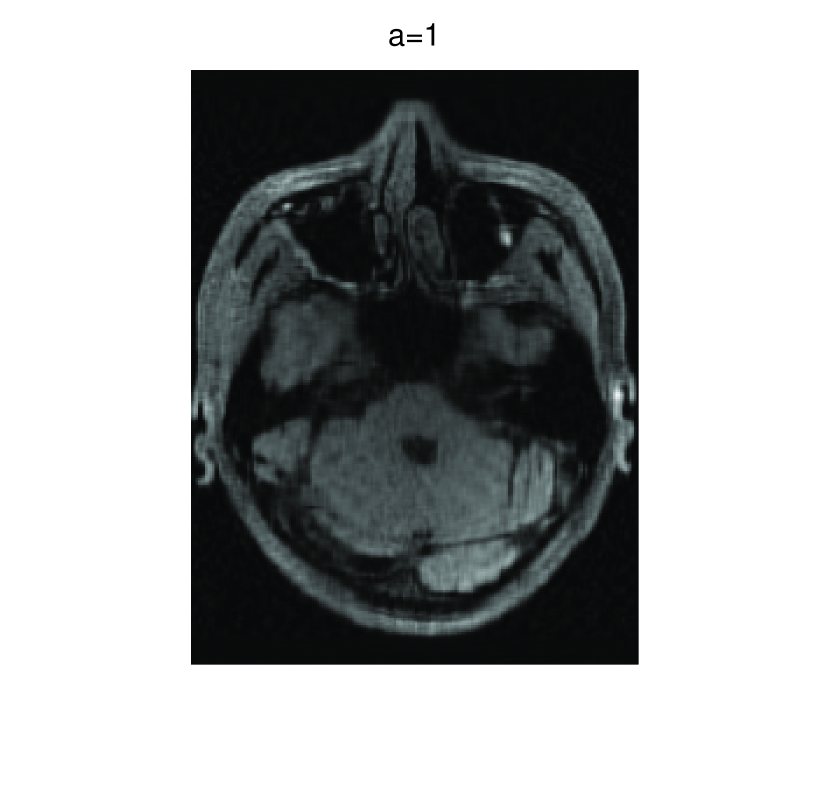

In this subsection, we demonstrate performances of ISVTA on image inpainting problems. The ISVTA is tested on some medical grace images (255×192255192255\times 192 Brain angiography image (BAI), 395×549395549395\times 549 Hand angiography image (HAI) and 419×400419400419\times 400 Intracranial venous image (IVI)). We use the SVD to obtain their approximated low-rank images with rank r=30,40,30𝑟304030r=30,40,30, respectively. Numerical results of ISVTA for theses low-rank image inpainting problems are reported in Table 5, 6, 7, 8.

Figure 3: Original 255×192255192255\times 192 BAI and its approximation with rank 30.

Table 5, 6 show that ISVTA performs powerful in finding a low-rank matrix on image inpainting problems. Indeed, we could get an exact low-rank image by the ISVTA by choosing proper a𝑎a. Moreover, it is necessary to point out that our method does not work well for all a>0𝑎0a>0, and we can find that a=100𝑎100a=100 is not a good strategy for the low-rank IVI either SR=0.40SR0.40\mathrm{SR}=0.40 or SR=0.50SR0.50\mathrm{SR}=0.50. The numerical results of ISVT, SVTA and SVPA compared in Table 5, 6, 7, 8, 9, 10 under same circumstance show that the ISVT algorithm performs far more better than ISTA and SVPA on image inpainting problems for some proper a>0𝑎0a>0.